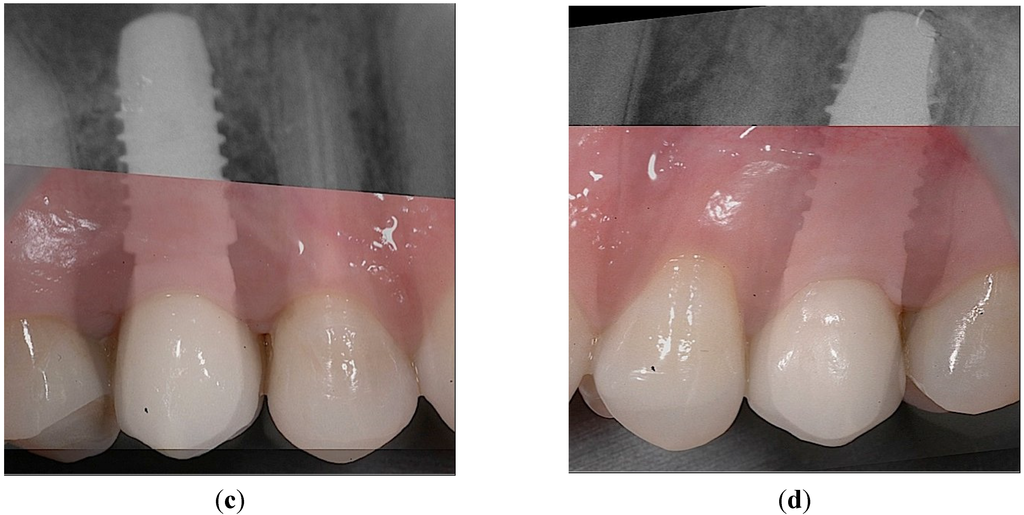

Figure 6.

Peri-apical X-rays at one-year follow-up. (a) Position 15; (b) Position 25.

Figure 7.

Intraoral views at one-year follow-up. (a) The optimal gingival margin was formed beneath the permanent crowns, both in the case of PFS, (b) as well as the StE implants. Superimposed clinical and X-ray pictures: (c) Position 15, PFS; (d) Position 25, StE.

The implants have been functionally loaded (AC) after six weeks. Corresponding peri-apical X-rays taken at this visit confirmed the absence of any pathological signs (Figure 5a,b; Positions 15 and 25, respectively).

Six months after study completion (at the one-year follow-up), osseointegration was checked radiographically. Both X-rays were free of any pathological signs (Figure 6a,b) with a quite satisfactory clinical outcome (Figure 7a–d). The outcome of this “split-jaw” case was equally positive for both the PFS (Position 15) and StE (Position 25) implants. In this respect, the case is representative of the entire trial patient population.